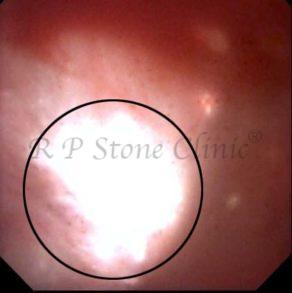

These images are taken as snap shots from the video recording of RIRS Surgery done at our hospital. These are Randall’s Plaques seen with Digital FLEX XC & Digital FLEX XC S. The cream or whitish patches are seen on the tips of RENAL PAPILLAE as seen in images below.

The Below Images Show Small Stones attached to the Renal Papillae.